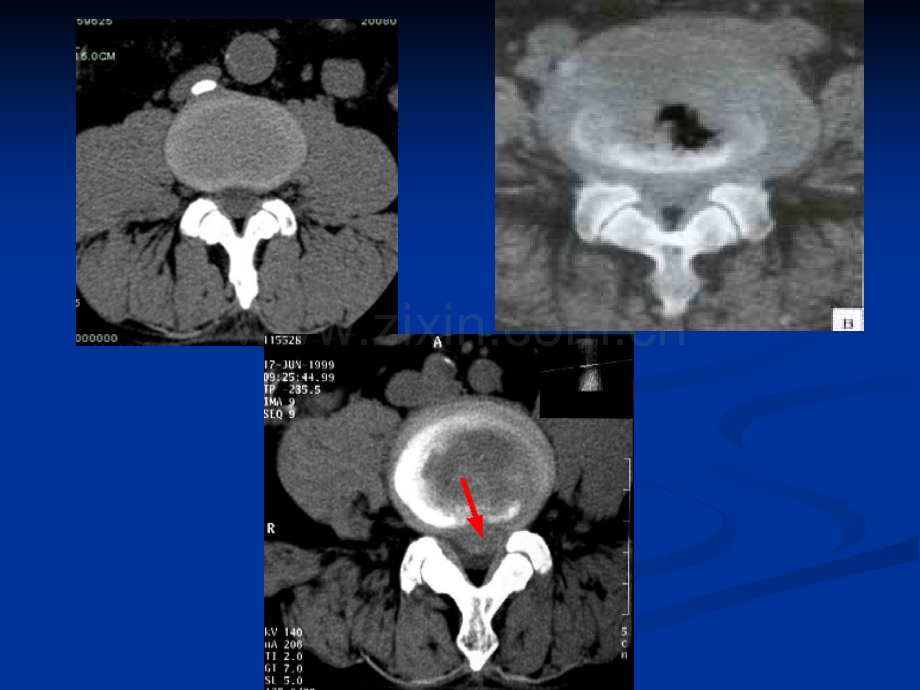

n n骨折线骨折线n n骨折类型骨折类型n n对位对线关系对位对线关系n n儿童骨折的特点儿童骨折的特点知识回顾二二骨与骨与软组织的感染的感染(一)化(一)化脓性骨髓炎性骨髓炎 是由化脓性细菌引起的骨感染。感染途径:血源性,邻近软组织直接蔓延,骨外伤感染后引起的骨内感染。(1 1 1 1)早期表早期表早期表早期表现现:软组织软组织改改改改变变;(2 2 2 2)发发病病病病2 2 2 2周后周后周后周后X X X X线线才可才可才可才可见见骨骼改骨骼改骨骼改骨骼改变变。(3 3 3 3)骨骨骨骨质质破坏破坏破坏破坏:uu多始于多始于多始于多始于干干干干骺骺端松端松端松端松质质骨骨骨骨,松,松,松,松质质骨局限性骨骨局限性骨骨局限性骨骨局限性骨质质疏疏疏疏松,松,松,松,继继而形成多而形成多而形成多而形成多发发不不不不规则规则小片状骨小片状骨小片状骨小片状骨质质破坏;破坏;破坏;破坏;uu沿骨干沿骨干沿骨干沿骨干发发展,表展,表展,表展,表现为现为骨破坏区骨破坏区骨破坏区骨破坏区扩扩大大大大。uu皮皮皮皮质质骨骨骨骨破坏。破坏。破坏。破坏。uu同同同同时时有骨有骨有骨有骨质质增生硬化增生硬化增生硬化增生硬化.(2 2)X线平片平片(4 4 4 4)骨膜反骨膜反骨膜反骨膜反应应:uu 表表表表现为现为与骨干平行的骨膜新生骨,可呈与骨干平行的骨膜新生骨,可呈与骨干平行的骨膜新生骨,可呈与骨干平行的骨膜新生骨,可呈单层单层条状、多条状、多条状、多条状、多层层状、花状、花状、花状、花边边状或三角形。状或三角形。状或三角形。状或三角形。(5 5 5 5)死骨死骨死骨死骨:uu表表表表现为现为沿骨沿骨沿骨沿骨长轴长轴的条形死骨,密度的条形死骨,密度的条形死骨,密度的条形死骨,密度较较周周周周围围骨骨骨骨质质高。高。高。高。发发病病3 3周周,骨,骨质质破坏明破坏明显显,骨,骨膜反膜反应应广泛且明广泛且明显显,死骨形成密,死骨形成密度高,与周度高,与周围围骨骨质质分界清楚。分界清楚。2慢性化脓行骨髓炎引起本病引起本病长期不愈的原因是期不愈的原因是死骨的存留死骨的存留X线表表现:以骨硬化增生为主。骨干变粗,髓腔消失,边缘不规则,密度增高;骨硬化区内可见透亮的脓腔及死骨。硬化性骨髓炎硬化性骨髓炎急慢性化脓性骨髓炎急慢性化脓性骨髓炎n n1 1、临床:、临床:、临床:、临床:n n2 2、骨质破坏与骨质增生:、骨质破坏与骨质增生:、骨质破坏与骨质增生:、骨质破坏与骨质增生:n n3 3、骨膜反应、骨膜反应、骨膜反应、骨膜反应n n4 4、死骨、死骨、死骨、死骨(三)骨与软组织肿瘤及瘤样病变诊断原则:影像学检查结合临床和病理检查是诊断骨肿瘤的正确途径。对骨肿瘤影像诊断的要求:1111、判断骨病、判断骨病、判断骨病、判断骨病变变是否是否是否是否为肿为肿瘤瘤瘤瘤2222、如是、如是、如是、如是肿肿瘤,判断良瘤,判断良瘤,判断良瘤,判断良恶恶性,原性,原性,原性,原发发性、性、性、性、转转移性移性移性移性3333、肿肿瘤的侵犯范瘤的侵犯范瘤的侵犯范瘤的侵犯范围围4444、推断、推断、推断、推断肿肿瘤的瘤的瘤的瘤的组织组织学学学学类类型型型型 重点在于判断重点在于判断重点在于判断重点在于判断肿肿瘤的良瘤的良瘤的良瘤的良恶恶性性性性良性骨良性骨良性骨良性骨肿肿瘤中:骨瘤中:骨瘤中:骨瘤中:骨软软骨瘤、骨瘤、骨瘤、骨瘤、骨巨骨巨骨巨骨巨细细胞瘤胞瘤胞瘤胞瘤恶恶性骨性骨性骨性骨肿肿瘤中:原瘤中:原瘤中:原瘤中:原发发性骨性骨性骨性骨肿肿瘤中瘤中瘤中瘤中骨肉瘤骨肉瘤骨肉瘤骨肉瘤最多最多最多最多见见继发继发性骨性骨性骨性骨肿肿瘤中瘤中瘤中瘤中转转移瘤移瘤移瘤移瘤最多最多最多最多见见1 1 1 1、年年年年龄龄与性与性与性与性别别:2020202040404040岁岁,男性多于女性,男性多于女性,男性多于女性,男性多于女性;2 2 2 2、部位部位部位部位:好:好:好:好发发于骨于骨于骨于骨骺骺已已已已闭闭合合合合的四肢的四肢的四肢的四肢长长骨骨端骨骨端骨骨端骨骨端,以股骨下端、以股骨下端、以股骨下端、以股骨下端、胫胫骨上端和骨上端和骨上端和骨上端和桡桡骨下端骨下端骨下端骨下端为为最好最好最好最好发发部部部部位。位。位。位。3 3 3 3、临临床表床表床表床表现现:局部:局部:局部:局部肿胀肿胀、疼痛、疼痛、疼痛、疼痛、压压痛。痛。痛。痛。4 4 4 4、病理分、病理分、病理分、病理分级级:良性、生:良性、生:良性、生:良性、生长长活活活活跃跃、恶恶性性性性(一)骨巨细胞瘤 X线表表现1 1 1 1、长长骨病骨病骨病骨病变变位于骨端,病位于骨端,病位于骨端,病位于骨端,病变变直达骨性关界面下直达骨性关界面下直达骨性关界面下直达骨性关界面下;2 2 2 2、偏偏偏偏侧侧性性性性、膨膨膨膨胀胀性性性性骨骨骨骨质质破破破破坏,瘤区坏,瘤区坏,瘤区坏,瘤区X X线线表表表表现现分两型:分两型:分两型:分两型:分房型、溶骨型分房型、溶骨型分房型、溶骨型分房型、溶骨型 分房型:分房型:破坏区内可有数量不等、比较纤细的破坏区内可有数量不等、比较纤细的骨嵴,似有分隔,成为大小不一的小房征。骨嵴,似有分隔,成为大小不一的小房征。溶骨型:溶骨型:破坏区内无骨嵴,仅表现为单一的骨破坏区内无骨嵴,仅表现为单一的骨质破坏。质破坏。溶骨型溶骨型其他征象:其他征象:局部骨骼膨大,皮质变薄,周围有一薄层骨壳。邻近无骨膜反应。若肿瘤生长较快,骨质明显破坏,周围出现软组织肿块,视为恶性。骨巨骨巨细胞瘤的胞瘤的恶变骨巨细胞瘤骨巨细胞瘤n n1 1、年龄:、年龄:、年龄:、年龄:20-4020-40岁岁岁岁n n2 2、部位:膝关节、腕关节周围、部位:膝关节、腕关节周围、部位:膝关节、腕关节周围、部位:膝关节、腕关节周围n n3 3、骨质破坏:偏心性、膨胀性骨质破坏,、骨质破坏:偏心性、膨胀性骨质破坏,、骨质破坏:偏心性、膨胀性骨质破坏,、骨质破坏:偏心性、膨胀性骨质破坏,内常有分隔内常有分隔内常有分隔内常有分隔n n4 4、恶变征象、恶变征象、恶变征象、恶变征象1 1 1 1、临临床要点:床要点:床要点:床要点:年年年年龄龄与性与性与性与性别别:多:多:多:多见见于于于于青少年青少年青少年青少年,1111111120202020岁岁多多多多见见,男性,男性,男性,男性较较多。多。多。多。部位部位部位部位:长长骨干骨干骨干骨干骺骺端端端端好好好好发发,以股骨下端,以股骨下端,以股骨下端,以股骨下端,胫胫骨上端和肱骨上端多骨上端和肱骨上端多骨上端和肱骨上端多骨上端和肱骨上端多见见。症状:局部症状:局部症状:局部症状:局部进进行性疼痛、行性疼痛、行性疼痛、行性疼痛、肿胀肿胀和功能障碍。和功能障碍。和功能障碍。和功能障碍。(二)原发性恶性骨肿瘤:骨肉瘤uu X X线线平片平片平片平片1 1 1 1、其基本其基本其基本其基本X X X X线线征象:征象:征象:征象:骨骨骨骨质质破坏破坏破坏破坏和和和和瘤骨瘤骨瘤骨瘤骨形成形成形成形成、骨膜新生骨及再破坏骨膜新生骨及再破坏骨膜新生骨及再破坏骨膜新生骨及再破坏、软组织肿块软组织肿块及其内及其内及其内及其内肿肿瘤骨瘤骨瘤骨瘤骨。2 2 2 2、根据骨破坏和骨增生根据骨破坏和骨增生根据骨破坏和骨增生根据骨破坏和骨增生的多少,分的多少,分的多少,分的多少,分为为成骨型成骨型成骨型成骨型、溶骨溶骨溶骨溶骨型型型型和和和和混合型混合型混合型混合型。(1 1 1 1)成骨型成骨型成骨型成骨型:以以以以骨骨骨骨质质增生硬化增生硬化增生硬化增生硬化为为主,主,主,主,瘤体是由密度高而不均瘤体是由密度高而不均瘤体是由密度高而不均瘤体是由密度高而不均匀的匀的匀的匀的肿肿瘤骨构成。瘤骨构成。瘤骨构成。瘤骨构成。往往在往往在往往在往往在软组织软组织中形成骨中形成骨中形成骨中形成骨性性性性肿块肿块,肺内,肺内,肺内,肺内转转移灶密移灶密移灶密移灶密度度度度较较高。高。高。高。(2 2 2 2)溶骨型溶骨型溶骨型溶骨型:病病病病变变以以以以骨破坏骨破坏骨破坏骨破坏为为主,破坏主,破坏主,破坏主,破坏区与正常骨之区与正常骨之区与正常骨之区与正常骨之间间界限不清,界限不清,界限不清,界限不清,皮皮皮皮质质破坏成破坏成破坏成破坏成筛筛孔孔孔孔样样,可出可出可出可出现现骨膜反骨膜反骨膜反骨膜反应应CodmanCodman三角三角三角三角,软组织肿块软组织肿块中很少中很少中很少中很少有有有有肿肿瘤骨。瘤骨。瘤骨。瘤骨。混合型:混合型:混合型:混合型:成骨与溶骨的程度大成骨与溶骨的程度大成骨与溶骨的程度大成骨与溶骨的程度大致相同。致相同。致相同。致相同。溶骨性破坏区和溶骨性破坏区和溶骨性破坏区和溶骨性破坏区和软组软组织肿块织肿块中可中可中可中可见较见较多的多的多的多的肿肿瘤骨瘤骨瘤骨瘤骨.肿肿瘤周瘤周瘤周瘤周围围可可可可见见不同程不同程不同程不同程度的骨膜增生。度的骨膜增生。度的骨膜增生。度的骨膜增生。右肱骨混合型骨肉瘤右肱骨混合型骨肉瘤 2222CTCT 显显示示肿肿瘤骨敏感。瘤骨敏感。显显示示肿肿瘤与瘤与邻邻近近结结构的关系构的关系较较好。好。显显示示肿肿瘤在髓腔的蔓延瘤在髓腔的蔓延较较好。好。右右髂骨骨肉瘤骨骨肉瘤骨肉瘤骨肉瘤n n1 1 1 1、年龄:青少年、年龄:青少年、年龄:青少年、年龄:青少年n n2 2 2 2、部位:干骺端、部位:干骺端、部位:干骺端、部位:干骺端n n3 3 3 3、X X X X线表现:骨质破坏和瘤骨形成、骨膜新生线表现:骨质破坏和瘤骨形成、骨膜新生线表现:骨质破坏和瘤骨形成、骨膜新生线表现:骨质破坏和瘤骨形成、骨膜新生骨及再破坏、软组织肿块及其内肿瘤骨。骨及再破坏、软组织肿块及其内肿瘤骨。骨及再破坏、软组织肿块及其内肿瘤骨。骨及再破坏、软组织肿块及其内肿瘤骨。n n4 4 4 4、分型:、分型:、分型:、分型:良恶性骨肿瘤的鉴别n n生生生生长长情况情况情况情况 生生生生长缓长缓慢慢慢慢生生生生长长迅速迅速迅速迅速n n局部骨局部骨局部骨局部骨质变质变化化化化 膨膨膨膨胀胀性骨性骨性骨性骨质质破坏破坏破坏破坏 浸浸浸浸润润性破坏性破坏性破坏性破坏n n骨膜反骨膜反骨膜反骨膜反应应 常无常无常无常无 多种不同形多种不同形多种不同形多种不同形式式式式n n周周周周围软组织围软组织改改改改变变 不侵及不侵及不侵及不侵及 软组织肿块软组织肿块n n转转移情况移情况移情况移情况 无无无无 有有有有良性良性恶性恶性n n1 1、正常影像表现、正常影像表现n n2 2、基本病变表现、基本病变表现n n3 3、骨折、骨折n n4 4、椎间盘突出、椎间盘突出n n5 5、急慢性化脓性骨髓炎:、急慢性化脓性骨髓炎:n n6 6、骨巨细胞瘤:、骨巨细胞瘤:n n7 7、骨肉瘤:、骨肉瘤:骨骼与肌肉系统小结第三章 呼吸系统胸部正常表现及基本病变前言前言 肺部易被肺部易被X X线穿透,有良好的自然对比,线穿透,有良好的自然对比,因而影像学检查应用广泛。因而影像学检查应用广泛。1 1、X X线胸片线胸片是胸部病变的首选方法;是胸部病变的首选方法;2 2、CTCT是胸部病变的最佳方法;是胸部病变的最佳方法;3 3、MRIMRI常用于纵隔的显示;常用于纵隔的显示;4 4、DSADSA可清晰显示血管。可清晰显示血管。第二节第二节 正常影像表现正常影像表现一、正常一、正常X线、线、CT表现表现(一)胸廓:(一)胸廓:、软组织胸廓锁骨上皮肤皱、软组织胸廓锁骨上皮肤皱褶与胸锁乳突肌;胸大肌;乳房及乳头。褶与胸锁乳突肌;胸大肌;乳房及乳头。、骨性胸廓肋骨;锁骨;肩、骨性胸廓肋骨;锁骨;肩胛骨;胸骨及胸椎。胛骨;胸骨及胸椎。、胸膜叶间裂、胸膜叶间裂胸锁乳突肌、锁骨上皮肤皱褶胸锁乳突肌、锁骨上皮肤皱褶乳腺叶间胸膜:右水平裂n n肩胛骨肩胛骨(二)肺(二)肺、肺野内、中、外带,、肺野内、中、外带,上、中、下肺野。上、中、下肺野。、肺门构成、肺门构成 高度及肺门角高度及肺门角 肺门n n 3 3、肺纹理肺纹理:在充满气体的肺野,可见自肺门:在充满气体的肺野,可见自肺门向外呈放射状分布的树枝状影,称肺纹理。主要向外呈放射状分布的树枝状影,称肺纹理。主要为肺动脉的分支。为肺动脉的分支。4、肺叶、肺叶右肺分上、中、下三叶右肺分上、中、下三叶;左肺分上、下二叶左肺分上、下二叶;5、气管与支气管、气管与支气管6、横膈、横膈7、纵隔、纵隔n n1 1、纵隔位于胸骨之后,胸椎之前,两肺之间,、纵隔位于胸骨之后,胸椎之前,两肺之间,将胸腔分为左右两半将胸腔分为左右两半;n n2 2、纵隔上界为胸腔入口,下界为膈,两侧为、纵隔上界为胸腔入口,下界为膈,两侧为纵隔胸膜和肺门纵隔胸膜和肺门;n n3 3、纵隔、纵隔内容物内容物:心脏、血管、气管支气管、:心脏、血管、气管支气管、食管、胸腺、淋巴结、神经、脂肪等食管、胸腺、淋巴结、神经、脂肪等;n nCTCT观察胸部,需两种不同的窗宽和窗位:观察胸部,需两种不同的窗宽和窗位:肺窗和纵隔窗肺窗和纵隔窗右股骨慢性化右股骨慢性化脓性骨髓炎性骨髓炎